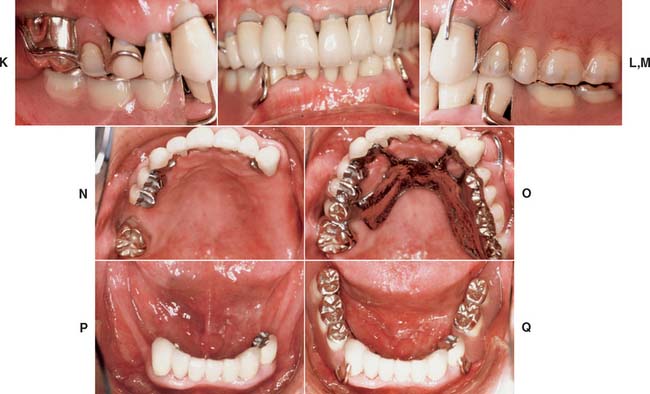

Fig. 32-38 Full-mouth rehabilitation with fixed, implant-supported, and removable partial prosthodontics (Treatment VI). Before treatment: Note the reverse smile line and discrepancy in the maxillary central incisor gingival tissue levels. The maxillary first molars had furcation involvement and poor prognosis as a result of periodontal bone loss. A and B, Occlusal views. C, Frontal view. D and E, Right and left views in maximum intercuspation. F, Diagnostic waxing. G, Dental implants were placed to restore the mandibular arch and provide retention and support for a maxillary partial removable dental prosthesis (RDP). H, The gingival tissue levels were corrected with periodontal surgery. I and J, Anterior teeth prepared for fixed restorations. After treatment: K and L, Occlusal views of maxillary arch with and without partial RDP. M, Occlusal view of restored mandibular arch. N and O, Right and left mirror views in maximum intercuspation. P, Frontal view.

Fig. 32-42 This patient presented with multiple failing restorations and severely compromised function (Treatment X). A to E, Preoperative photographs. F to J, Posttreatment photographs. Where possible, I-bars were used to minimize clasp visibility. Also note the extensive use of metal occlusal surfaces. When prostheses are designed for dentitions with compromised crown/root ratios, precise adjustment of the occlusion and anterior guidance components is critical. K to Q, Seventeen-year follow-up photographs. Note that the maxillary canine was lost and the existing retainer was modified into a pontic through the addition of composite resin. Additional endodontic treatment was needed as time passed. R, Preoperative radiographs. S, Postoperative radiographs. T, Eight-year postoperative radiographs. U, Seventeen-year postoperative radiographs. A fixed dental prosthesis (FDP) was fabricated, replacing the missing tooth #3 with teeth #5, #4, and #2 as abutments. The teeth were prepared with minimal taper, and the castings exhibited good retention. After 10 years, the FDP failed when tooth #2 became dislodged, possibly as a result of the additional loading by the removable dental prosthesis (RDP). Tooth #2 and the pontic were removed, endodontic treatment was performed, a new crown was fabricated, and the #3 pontic was incorporated in a new RDP. Tooth #6 was lost as a result of internal resorption and caries. Initially, the tooth was discolored, but the lesion was inactive, and the attempt to save it failed after 8 years. Its guarded prognosis was discussed as a significant risk factor before treatment initiation. This suggests that teeth with a guarded prognosis can be maintained if attention is paid to the principles of casting adaptation and occlusion.